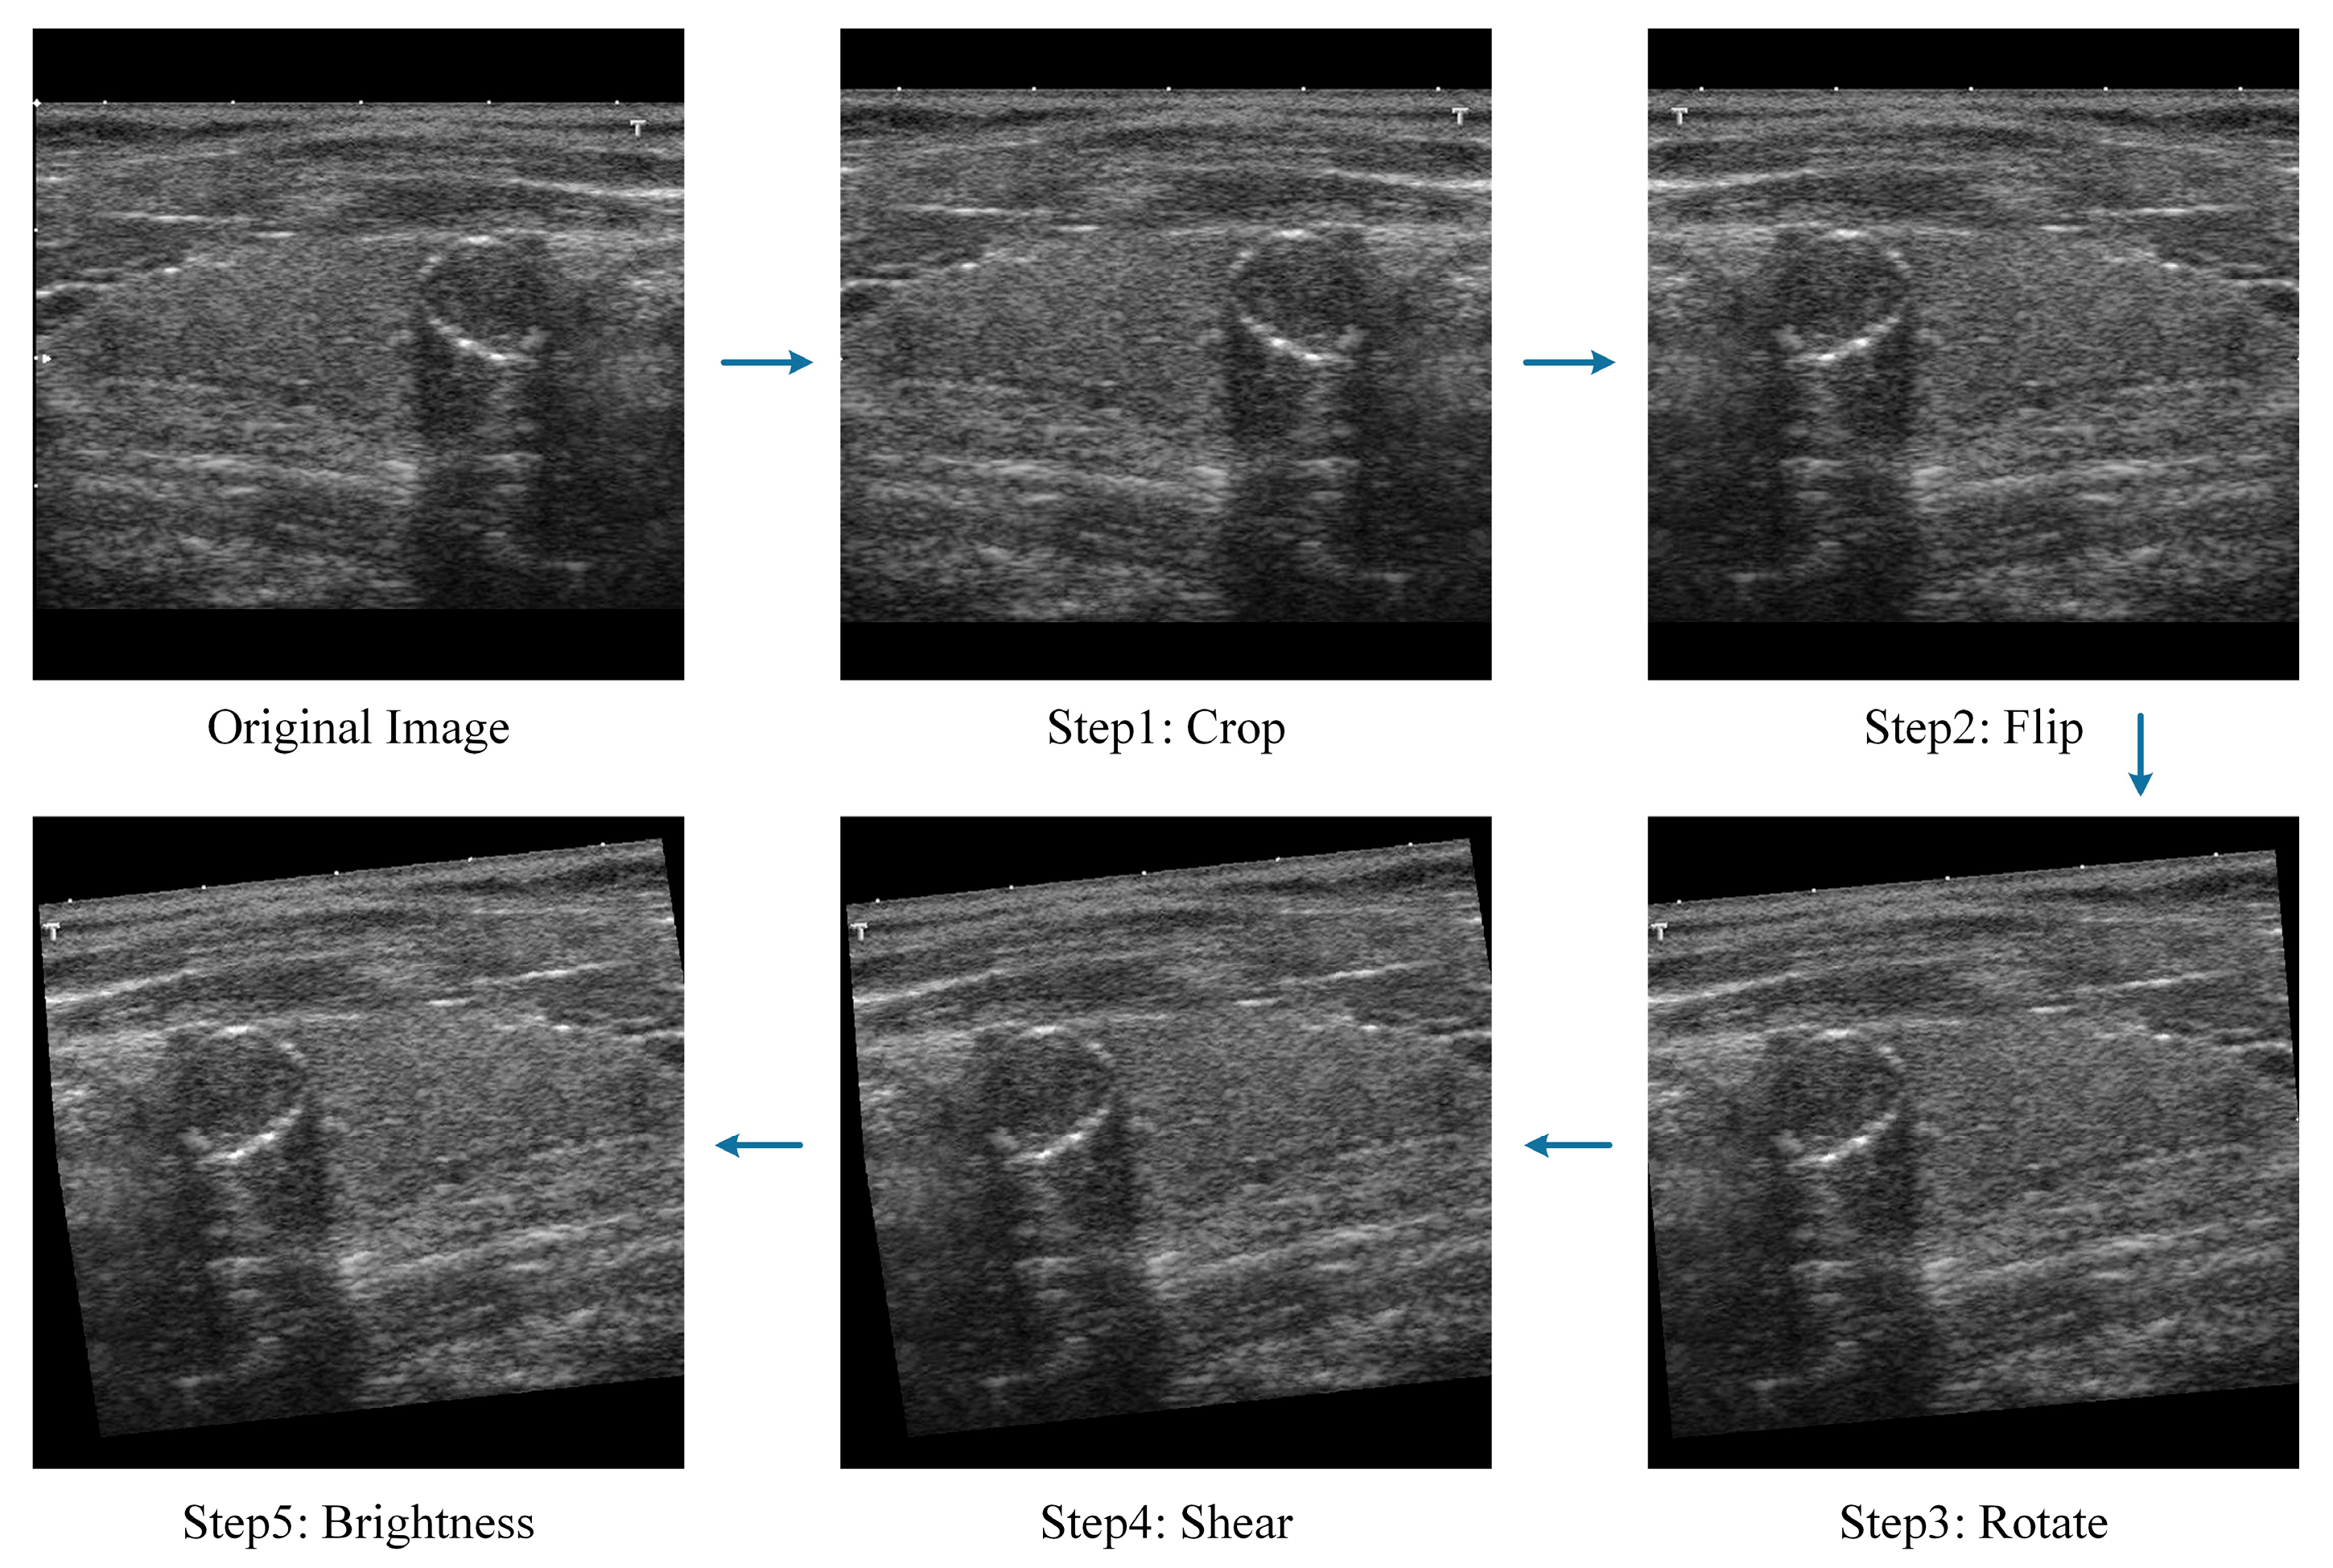

2.1.2. Data Preprocessing